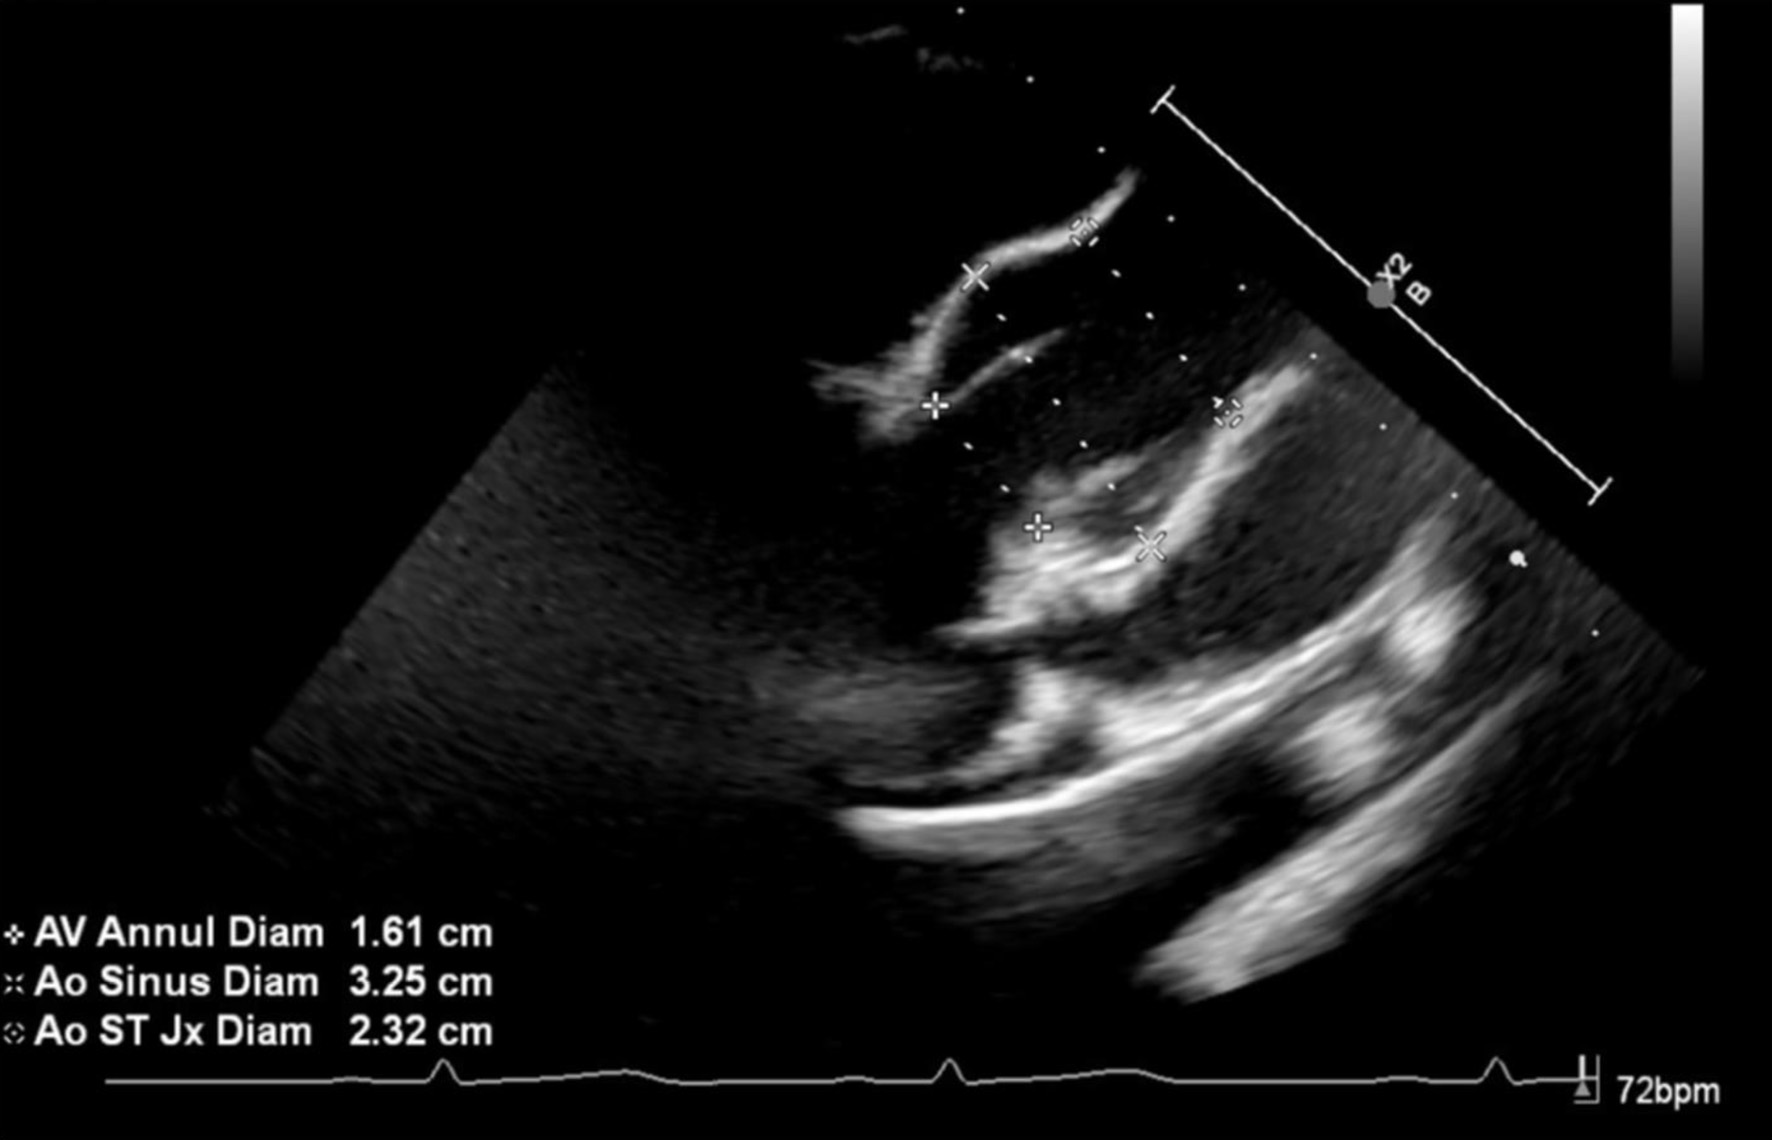

Review of this case and presentation in this format followed the guidelines of the Institutional Review Board of Nationwide Children’s Hospital. The study was conducted in compliance with the ethical standards of the responsible institution on human subjects as well as with the Helsinki Declaration. The patient was an 11-year, 2-month-old, 24.2 kg male presenting for a PSF with instrumentation from T11-L3 to treat scoliosis. The diagnosis of Beals syndrome was initially confirmed during his early childhood in China, but as he was adopted, specific information was lacking. At 6 years of age, he came to the United States and the diagnosis was confirmed based on the physical exam and radiographic findings. Physical findings included a right paraspinal prominence when bending forward and a lumbar moderate left-sided paraspinal prominence with a kyphotic component. His fingers had significant clinodactyly and camptodactyly. His feet were long and slender. Along with a severe 63° kyphoscoliosis, spinal imaging showed a hypoplastic L1 vertebral body with short pedicles partnered with degenerative changes of the L1/L2 disc (Fig. 1). Other comorbid conditions included a dilated aortic root, post traumatic stress disorder, and multiple contractures of the upper and lower extremities bilaterally. An echocardiogram noted the aortic root be severely dilated with trivial aortic valve regurgitation, moderate dilation of the ascending aorta, and normal biventricular size and systolic function (Fig. 2). He had a history of two previous anesthetic events for general anesthesia during magnetic resonance (MR) imaging with reports of emergence delirium. Additionally, during the second MR under general anesthesia, neck flexion resulted in airway obstruction despite the presence of an oral airway. This led to the decision to place an air-Q size 1.5 laryngeal mask airway (LMA) which allowed neck flexion for imaging without airway obstruction. Current medications included losartan (12.5 mg twice a day) for blood pressure management related to aortic root dilatation and cetirizine (5 mg once a day) as an anti-histamine for season allergies. Preoperative physical examination revealed a Mallampati Class II airway with normal mouth opening. There was limitation of neck flexion and extension. Respiratory and cardiac examinations were unremarkable. Preoperative laboratory evaluation including coagulation function, complete blood count, electrolytes, blood urea nitrogen, and creatinine was within normal limits. The patient was held nil per os for 6 h and transported to the operating room where standard American Society of Anesthesiologists’ monitors were placed. Anesthesia was induced by the inhalation of incremental concentrations of sevoflurane in air and oxygen with the maintenance of spontaneous ventilation. A peripheral intravenous cannula (18 gauge) was placed. Once adequate bag-valve-mask ventilation was demonstrated, propofol (30 mg) and rocuronium (20 mg) were administered. The trachea was intubated with a 6.0 mm cuffed endotracheal tube (ETT) using indirect videolaryngoscopy with a Glidescope® laryngoscope. There was a grade I laryngoscope view with full view of the glottis. Following the induction of anesthesia and endotracheal intubation, a second peripheral intravenous cannula and an arterial cannula (radial artery) were placed. The patient was turned prone onto the operating room table and positioned with padding of pressure points. To facilitate neurophysiological monitoring per our usual clinical practice and intraoperative pathway, maintenance anesthesia included desflurane titrated to maintain the bispectral index at 50 - 60, a remimazolam infusion (5 - 15 µg/kg/min), methadone (1.2 mg) followed by a remifentanil infusion adjusted from 0.05 to 0.3 µg/kg/h to maintain the mean arterial pressure at 55 - 65 mm Hg, and lidocaine (1 mg/kg/h) [4]. Measures to limit intraoperative blood loss and the need for the administration of allogeneic blood included controlled hypotension, intraoperative cell salvage, and tranexamic acid (50 mg/kg bolus dosing followed by 5 mg/kg/h). Surgical site prophylaxis was provided by cefazolin (50 mg/kg) every 3 h. Dexamethasone (4 mg) and ondansetron (3 mg) were administered to prevent postoperative nausea and vomiting. There were no adverse intraoperative events. The total fluid intake was 1,500 mL including 250 mL of 5% albumin (250 mL) and 1,250 mL of Normosol®-R electrolyte solution. Intraoperative urine output was 825 mL and estimated blood loss was 50 mL. At the completion of the surgical procedure, residual neuromuscular blockade was reversed with sugammadex, the patient was turned supine, and his trachea extubated when he followed commands. Postoperative analgesia included hydromorphone delivered via a patient-controlled device, intravenous acetaminophen every 6 h, intravenous ketorolac every 6 h, and a lidocaine infusion (1 mg/kg/h for the initial 24 postoperative hours). The patient was transported to the post-anesthesia care unit and then admitted to the inpatient ward. No postoperative respiratory issues were noted. The postoperative course was uneventful, and he was discharged home on postoperative day 2.

Click for large image

Figure 2. Preoperative echocardiograph image showing severe dilatation of the aortic root.

When compared to Marfan’s syndrome, anatomical cardiac defects are less frequent and tend to be anatomically less severe in patient with Beals syndrome. Congenital cardiac defects occur in approximately 15% of patients with Beals syndrome, the most common being aortic root dilation and mitral valve prolapse, and atrial/ventricular septal defects. Less common abnormalities may include atrial/ventricular septal defects and interrupted aortic arch. Aortic root dilation tends to be milder than that seen in Marfan’s syndrome, which tends to have measurements of more than 2 standard deviations above the mean [21]. In addition to structural defects, an isolated case report noted transient cardiomyopathy with balloon-like dilation of the left ventricle [22]. Given these concerns, preoperative echocardiography is suggested.